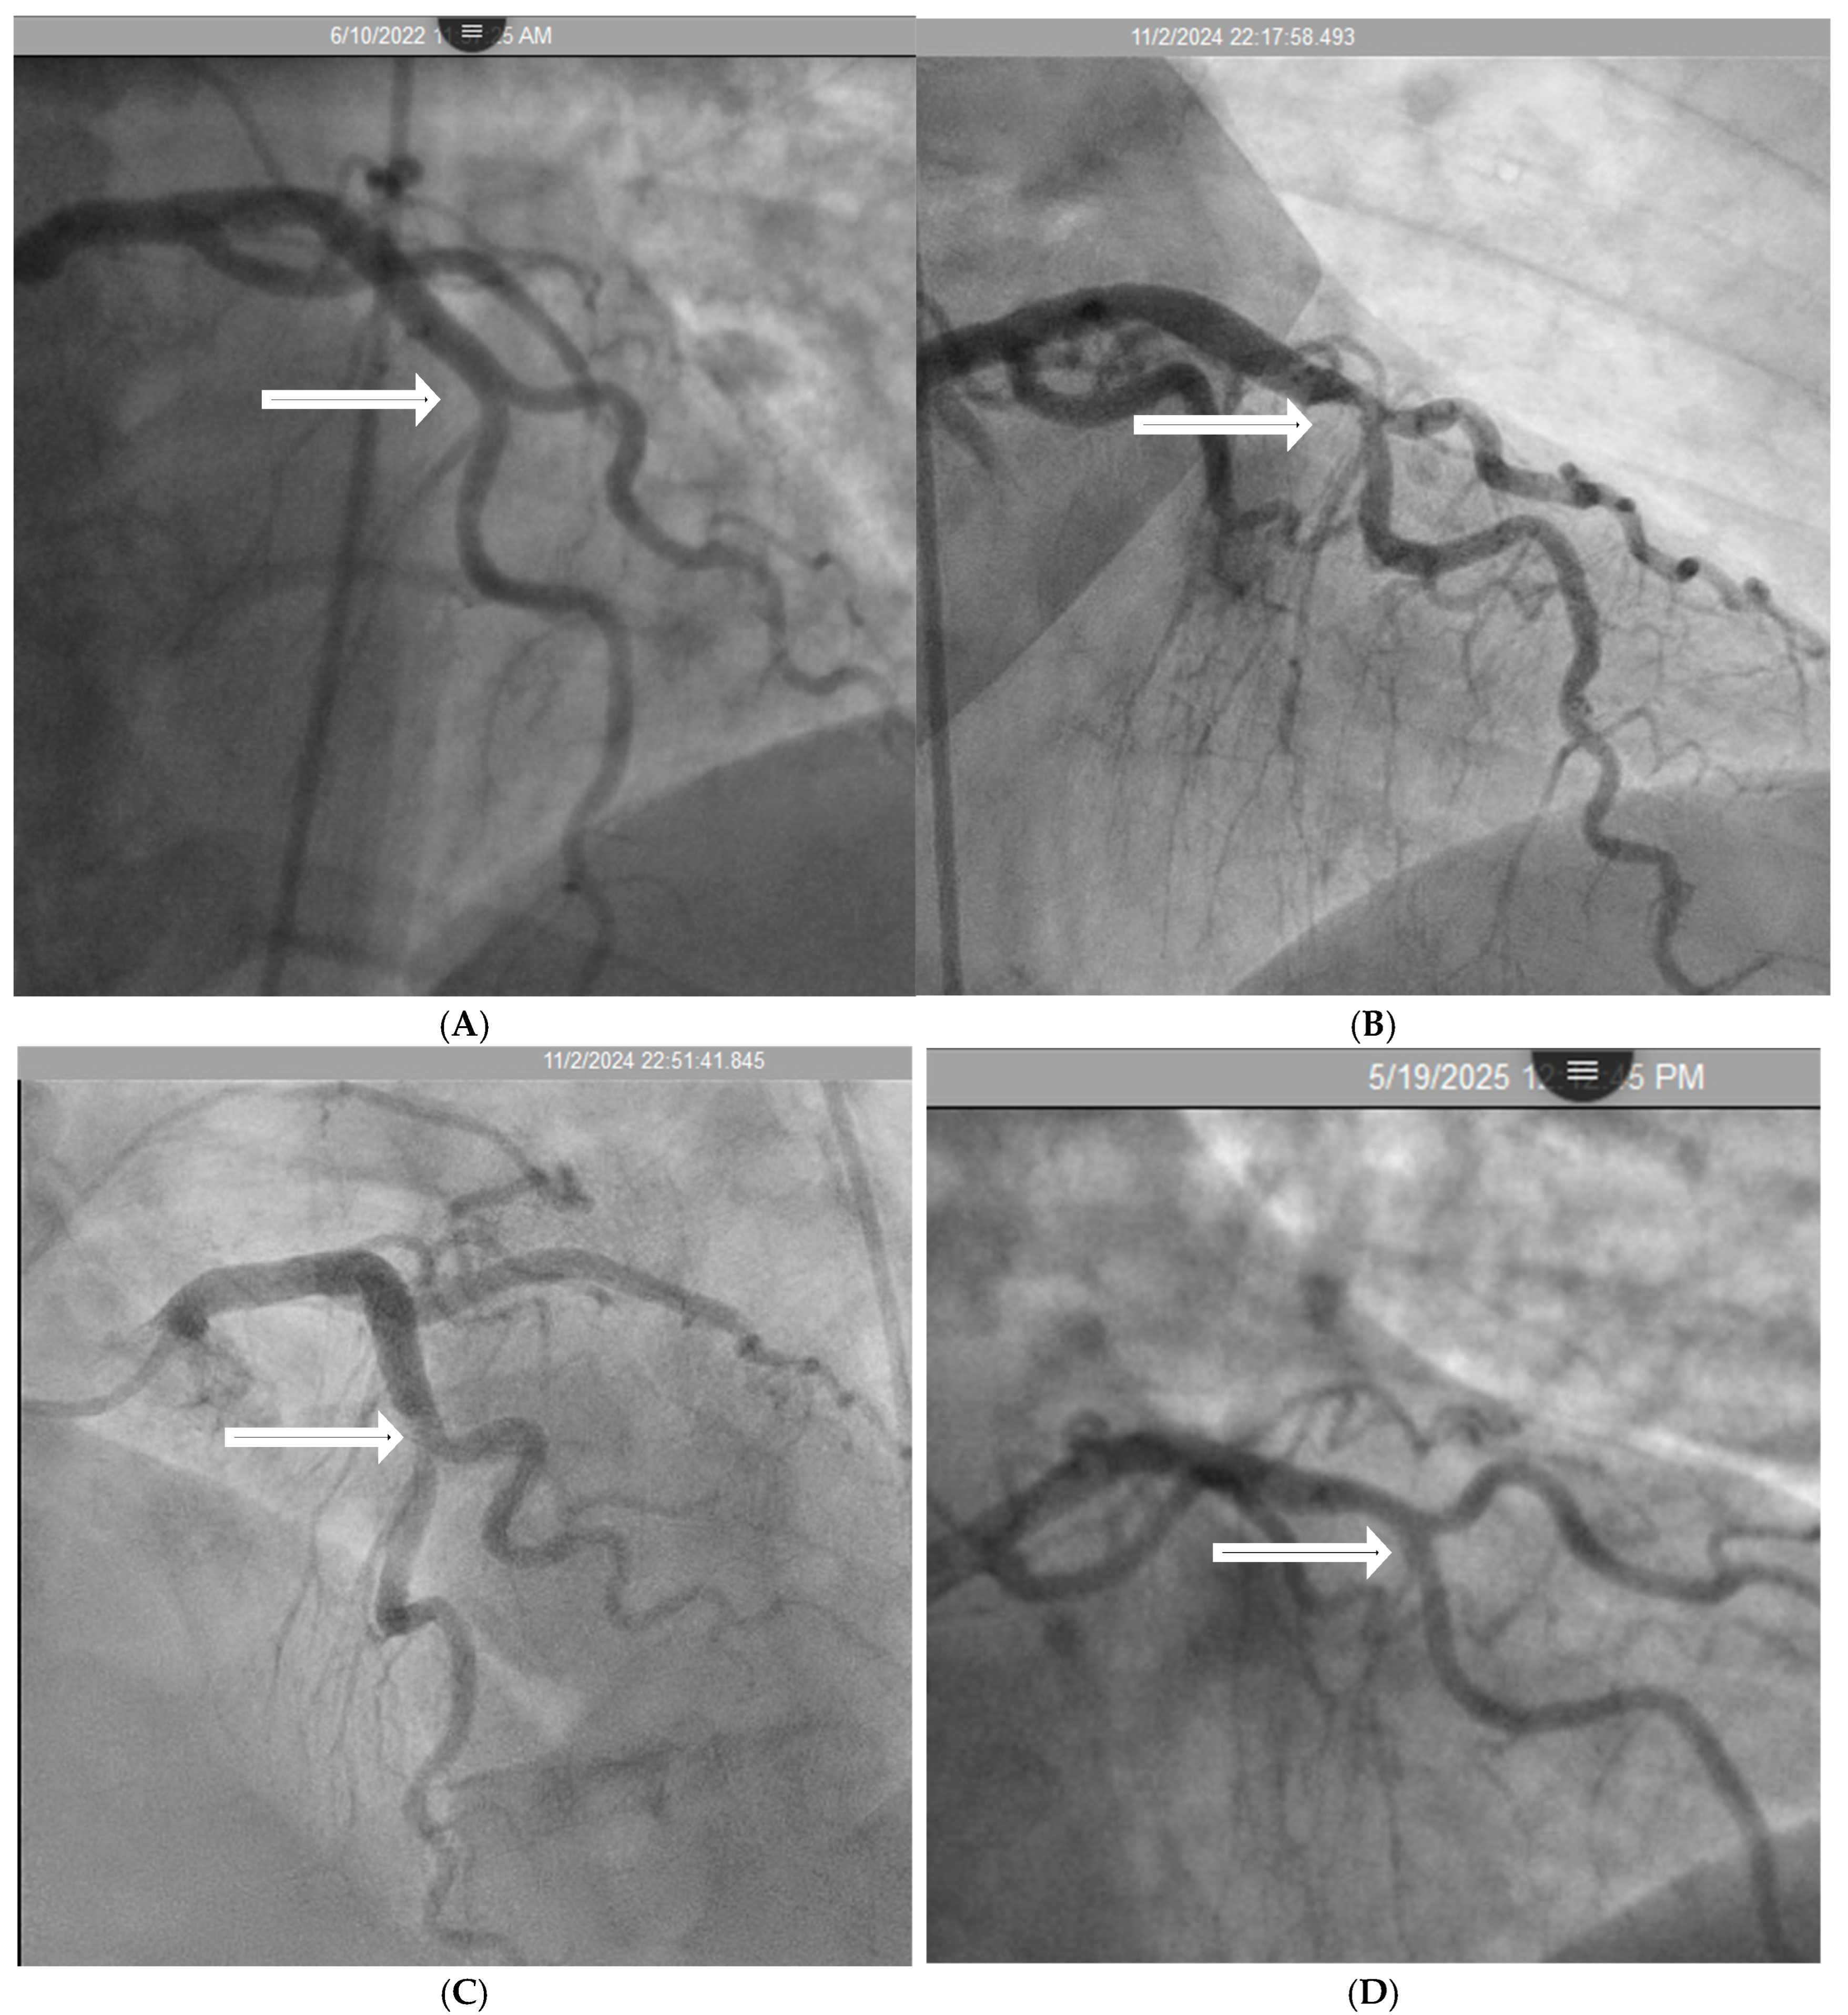

1. Introduction

2. Investigations for a Scientific Basis

2.1. Classifications

2.2. Mechanical Stress Due to Repetitive Bending at a Hinge Location

- Mechanics Perspective:

- Hinge Movement in Coronary Arteries:

2.3. Local Intimal Ischemia Due to Thick Boundary Layer

- Fluid Mechanics Perspective:

- Coronary Angiographic Perspective:

2.4. Recirculating Flow

2.5. Collision Secondary to Water Hammer Shock

- Coronary Dynamics Perspective:

- Acoustics Analysis of In Vitro Studies:

- Acoustic Analysis of Coronary Angiographic Flow:

- Acoustic Mechanisms of Coronary Injuries:

2.6. Codification of Lesions and Creation of a Coronary Acoustic Map